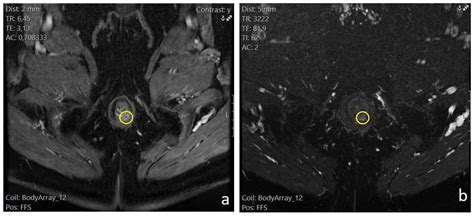

While looking for an image of anus fistula online might show you what the exterior opening looks like, it cannot reveal the depth or the complexity of the internal tract. Fistulas are categorized based on their path relative to the anal sphincter muscles, which is why clinical examination via imaging techniques like MRI or endorectal ultrasound is far more reliable than visual comparison alone.

• MRI: The gold standard for identifying complex or branching fistula tracts.